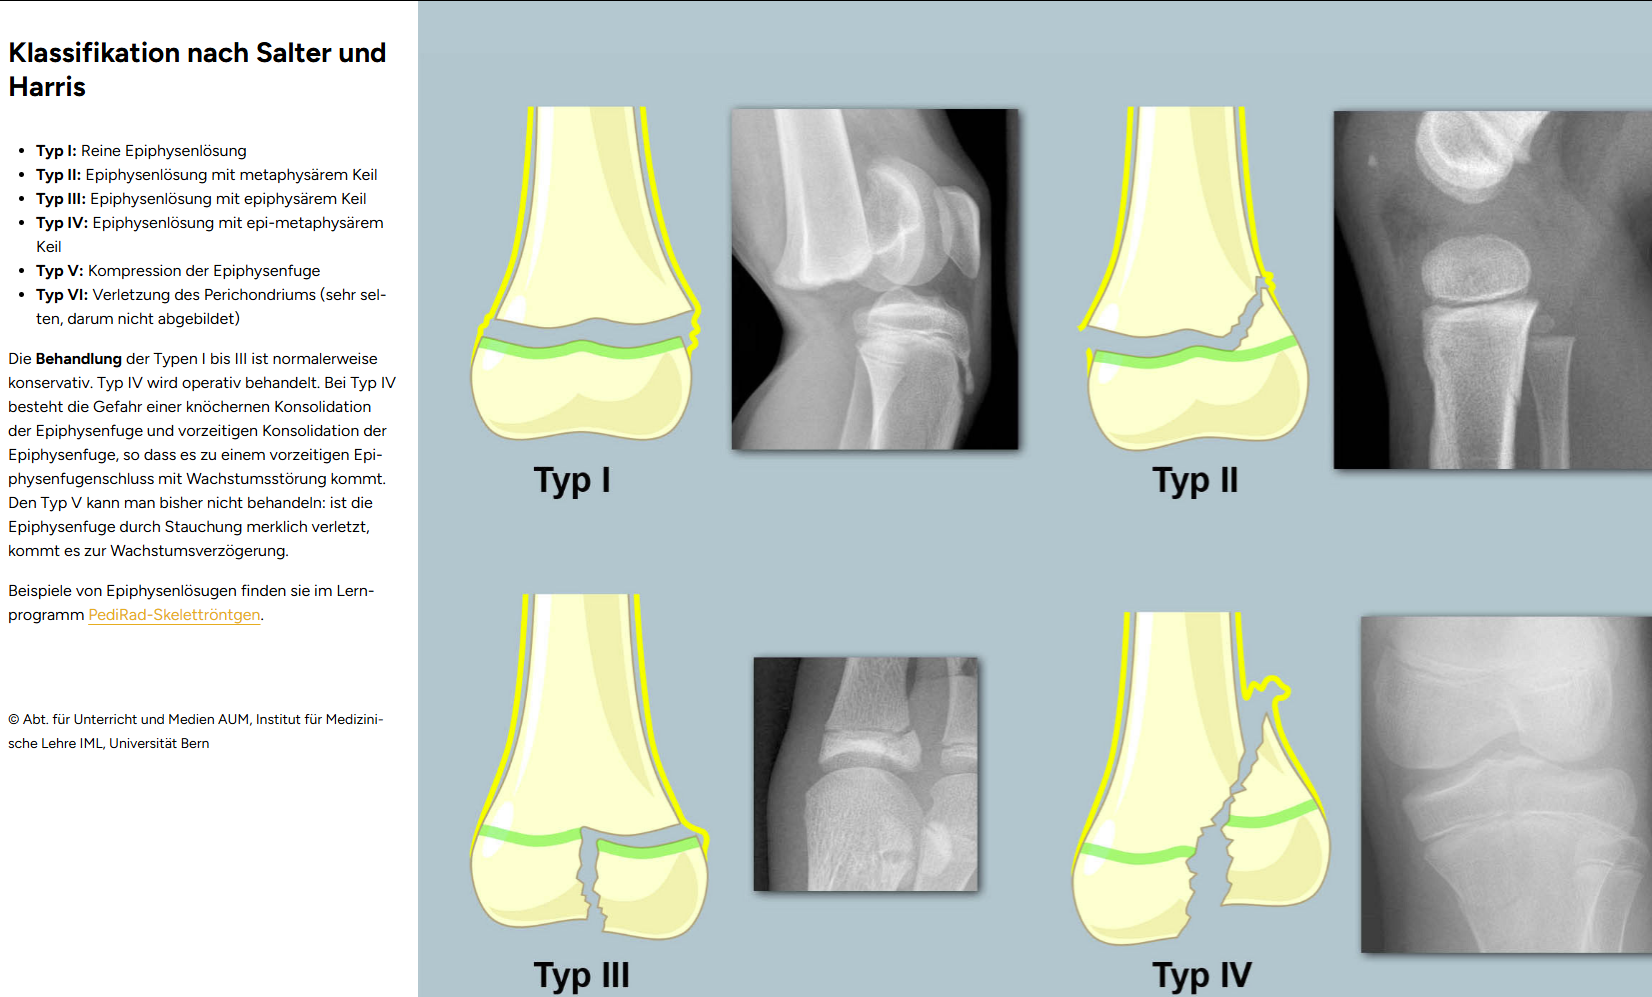

Foto Salter Harris